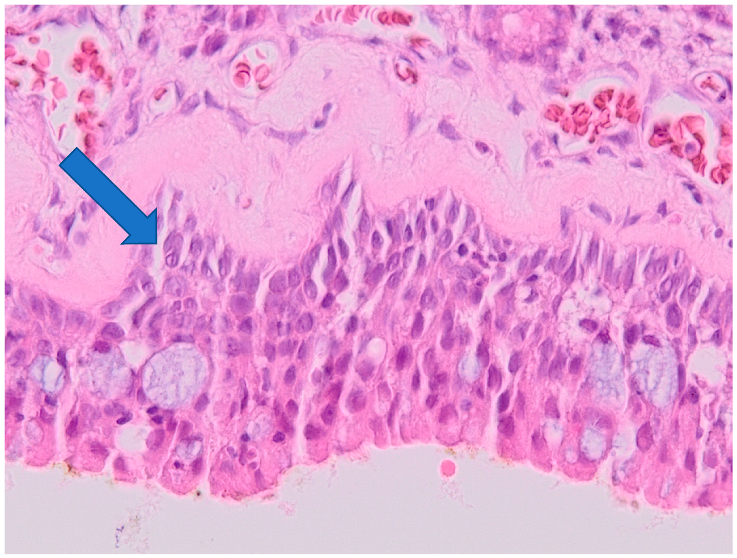

- 0

- Epithelial hyperplasia;

- 2

- Epithelial hyperplasia with mild signs of inflammation;

3.2. Histology

3.3. Correlation of Histology and Detected Compounds